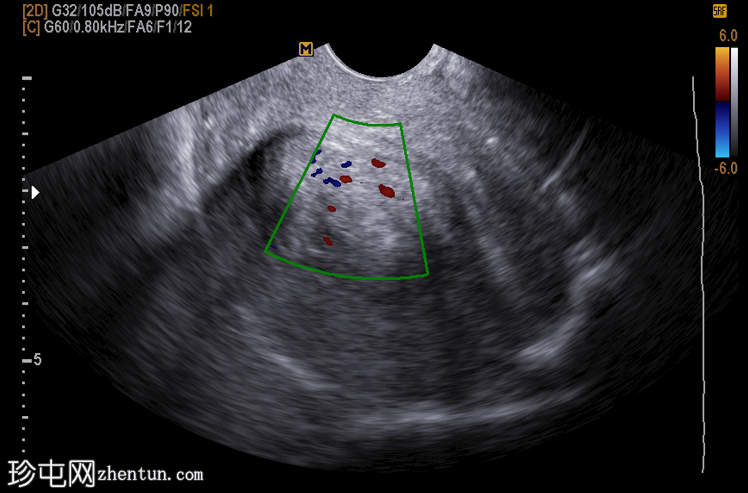

经阴道超声显示:

子宫内膜内可见边界清晰的卵圆形宫腔内病变

回声均匀,较子宫肌层高回声

周围有子宫内膜积液

彩色多普勒显示中央供血血管(供血动脉征)

彩色多普勒显示,息肉通常仅显示一条中央供血血管,而肌瘤则可见周围和/或多条血管通道。保持子宫内膜-子宫肌层界面光滑也有利于息肉的形成。